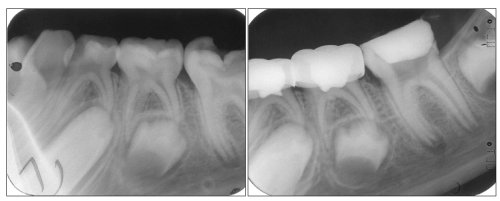

The clinical and radiographic success rates for the electrofulguration group were 95% and 85%, respectively, and for the formocresol group, 100% and 90%, respectively. Figures 1-4 show radiographs of one successful case for each of the two groups. Although the electrofulguration group radiographic failure rate was more than that of the formocresol group, this difference was not statistically significant at the P > 0.05 level using Fisher’s exact test.

Figure 1: Pre (a) and immediate postoperative (b) radiographs of an electrofulguration pulpotomized tooth (mandibular

left second primary molar) and a formocresol pulpotomized tooth (mandibular left first primary molar).

View Figure 1